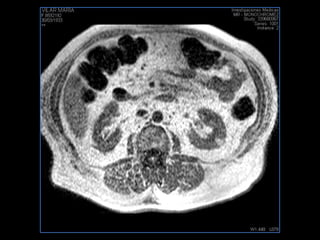

PROTOCOLO pancreas/ riñon AXIAL fat sat /AX in phase out phase AX T1 +SAG T2  COR T2, CON   GADOLINIO :  COR T1+AX T1(DIN) SAT: NO  FASE: RL THK: 4MM  COIL:  GAP: (FACTOR 1.4) 1MM FOV: 40 CM NEX:2 SINCRONIZACION RESPIRATORIA EN 3 O 4 CICLOS ALE

resonancia de abdomen